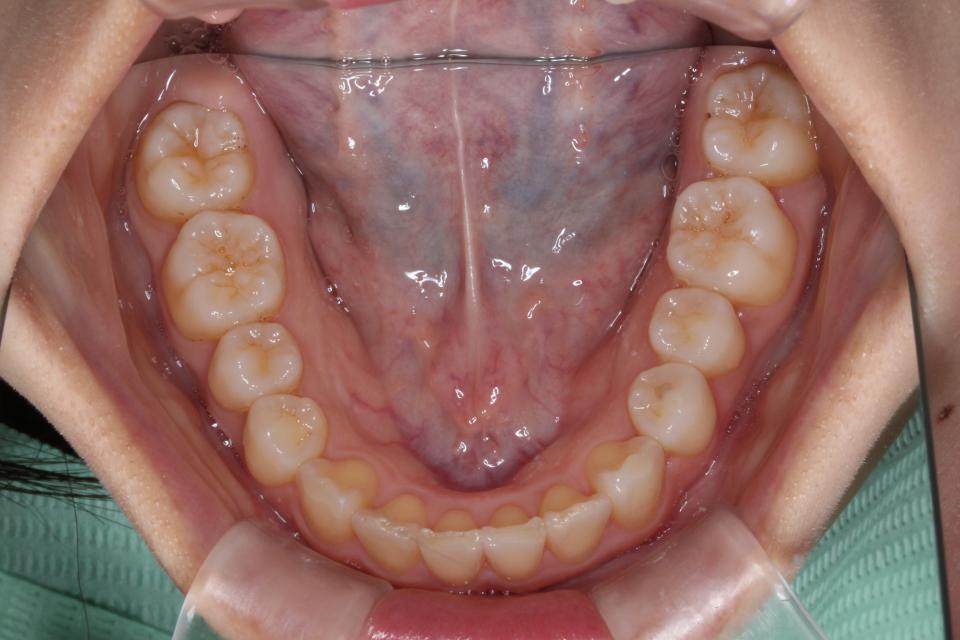

上顎前突(出っ歯)のマウスピース矯正治療例(抜歯あり)

矯正治療前

矯正治療後

20代女性の患者さんです。

歯並びのガタガタと出っ歯気になり矯正治療を始めました。

左上4番目の歯を抜歯して、マウスピース型の矯正治療装置を使用し、歯のやすり掛け(IPR)を行いました。

現在はマウスピース型のリテーナーで後戻りの防止をして定期的にチェックをしています。